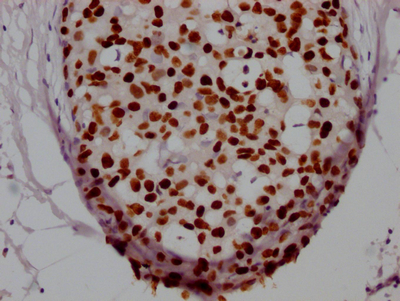

IHC image of CSB-RA246102A0HU diluted at 1:100 and staining in paraffin-embedded human breast cancer performed on a Leica BondTM system. After dewaxing and hydration, antigen retrieval was mediated by high pressure in a citrate buffer (pH 6.0). Section was blocked with 10% normal goat serum 30min at RT. Then primary antibody (1% BSA) was incubated at 4℃ overnight. The primary is detected by a Goat anti-rabbit IgG polymer labeled by HRP and visualized using 0.05% DAB.